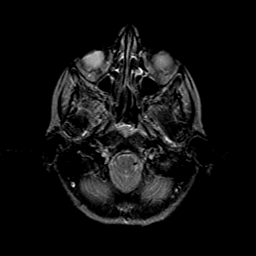

Metastatic bronchogenic carcinoma: T2-weighted MR -- Slice #2

[Home][Help][Clinical] Slice 2